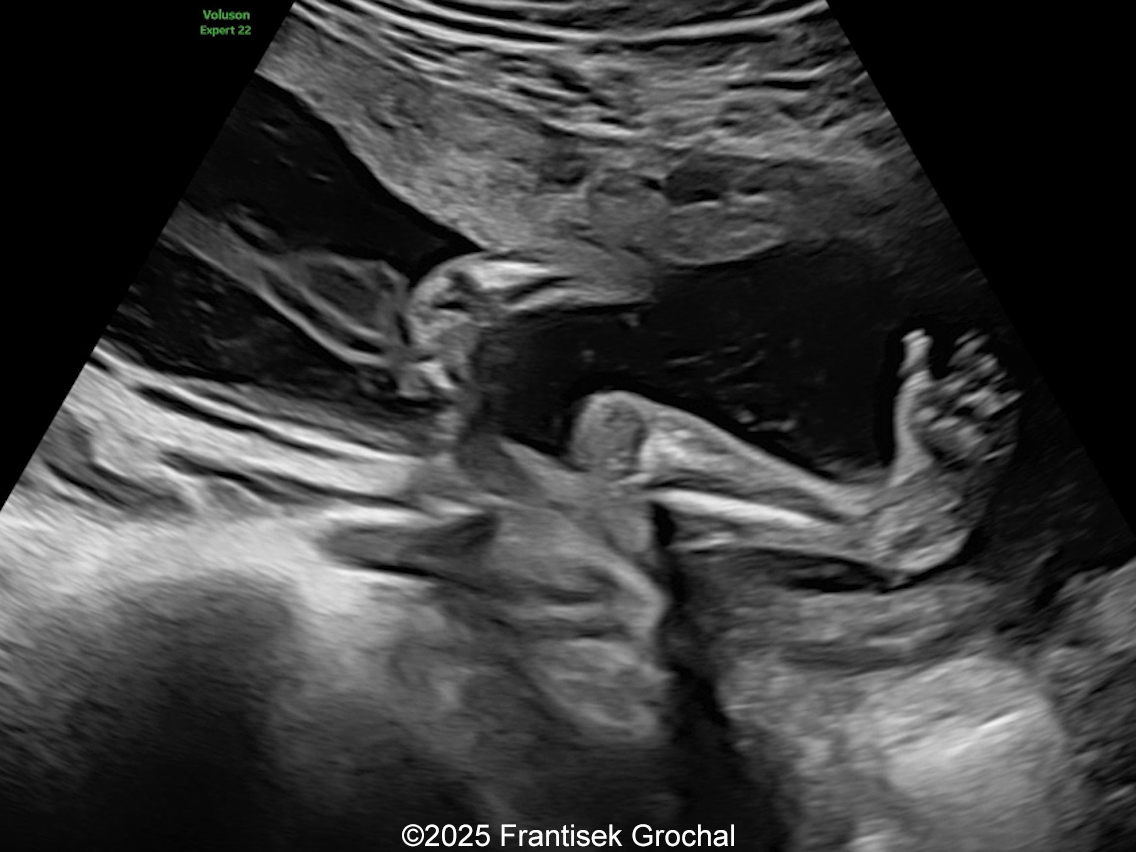

Image 1

We present a case of Amniotic Band Sequence seen in 21st week of pregnancy. The fetus showed the following findings:

• Constriction of fetal torso by two strips of amniotic band

Constriction of fetal torso by two stripes of the amniotic bands

Image 1 Constriction of fetal torso by two stripes of the amniotic bands

Image 3 Constriction of fetal torso by two stripes of the amniotic bands